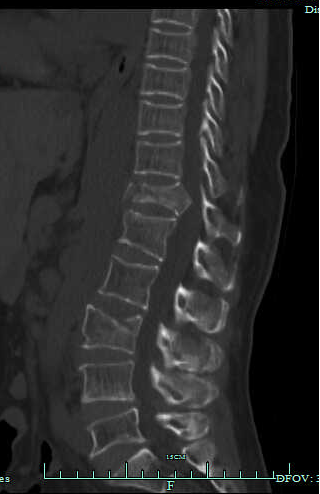

吴阿姨术后影像图

在麻醉科及手术室护理团队的精诚配合下,脊柱病区主任王建华带领团队对吴阿姨实施了「胸腰椎骨折后路椎管减压、骨折复位、长节段钉棒内固定+后外侧融合术」。历时3小时,手术在次日凌晨0时18分顺利结束。

积极手术是治疗的基础,术后的综合康复对吴阿姨来说同样至关重要。经过评估,王建华主任请高压氧舱和康复运动医学科会诊,共同促进吴阿姨神经功能恢复。在2个疗程的高压氧治疗,以及针灸、运动疗法、肌力训练及物理治疗后,术后1个月时,吴阿姨可以从床边坐起,双下肢主动抬高维持30秒以上,并逐渐能够在支具保护下尝试电动直立床站立训练,吴阿姨也转入了康复运动医学科,继续进行系统化的康复训练。术后6个月,经过骨科、康复运动医学科及高压氧等综合治疗,吴阿姨已经可以佩戴支具独立行走。